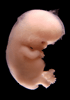

Carnegie Stage 22 (54 post-ovulatory days)

Most embryos at stage 22 are approximately 54 postovulatory days old and measure 25-27 mm in length. Distinguishing criteria for this stage include clear formation of the external ear, the hands begin to extend ventrally beyond the body wall, the fingers of one hand may overlap the fingers of the opposite hand, thickened eyelids just begin to cover the outer margins of the eye, and the superficial vascular plexus of the head now extends about three-quarters of the way above the eye-ear level.